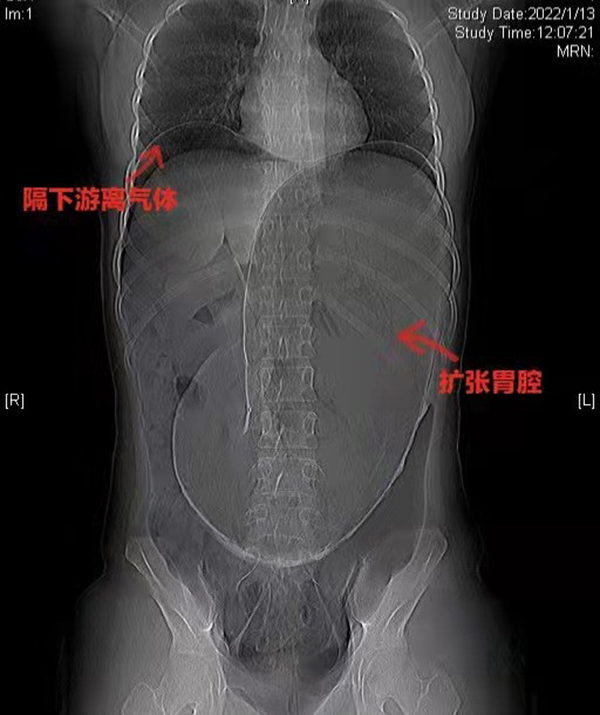

黃淮網(wǎng) 20222年1月13日,伴隨著急促的救護(hù)車?guó)Q笛聲,徐州醫(yī)科大學(xué)附屬醫(yī)院急診中心接診了一位特殊的患者。一位年輕的女性,肚脹如鼓,腹痛難忍。急診外科迅速完善初步檢查并聯(lián)系胃腸外科會(huì)診。此刻,時(shí)間就是花季少女的生命!胃腸外科張秀忠主任團(tuán)隊(duì)立刻投入到緊張有序的治療中。經(jīng)過(guò)問(wèn)診、查體、影像學(xué)檢查等綜合診斷后判定患者胃腔極度擴(kuò)張、膈下游離氣體,提示消化道穿孔。此時(shí)患者已有休克表現(xiàn),病情危急,隨時(shí)有生命危險(xiǎn),需急診手術(shù)處理。

徐醫(yī)附院胃腸外科團(tuán)隊(duì)同患者家屬進(jìn)行了必要的溝通之后,緊急進(jìn)入手術(shù)室進(jìn)行手術(shù)。監(jiān)測(cè)生命體征顯示患者處于感染性休克狀態(tài),在麻醉科王光磊主任的保駕護(hù)航下,張沖主任帶領(lǐng)團(tuán)隊(duì)人員經(jīng)過(guò)術(shù)中探查發(fā)現(xiàn)患者胃體積巨大充滿內(nèi)容物,約40*25厘米,胃及脾臟順時(shí)針旋轉(zhuǎn)360°,全胃呈缺血壞死表現(xiàn)伴胃小彎穿孔、脾梗死。術(shù)中告知患者家屬探查情況后,為患者進(jìn)行了全胃切除加脾臟切除術(shù)。術(shù)后,張秀忠主任嚴(yán)密觀察患者病情變化,制定治療方案,在患者生命體征平穩(wěn)后將其由重癥監(jiān)護(hù)室轉(zhuǎn)入胃腸外科病房。在醫(yī)護(hù)人員的共同努力下,患者病情好轉(zhuǎn)。目前患者恢復(fù)過(guò)程順利,近日可考慮出院。